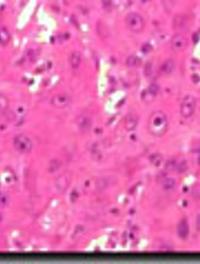

Au cours de la maladie d’Alzheimer, une immunisation vis-à-vis du peptide amyloïde bêta (Aβ42) utilisé dans son intégralité pourrait [...]